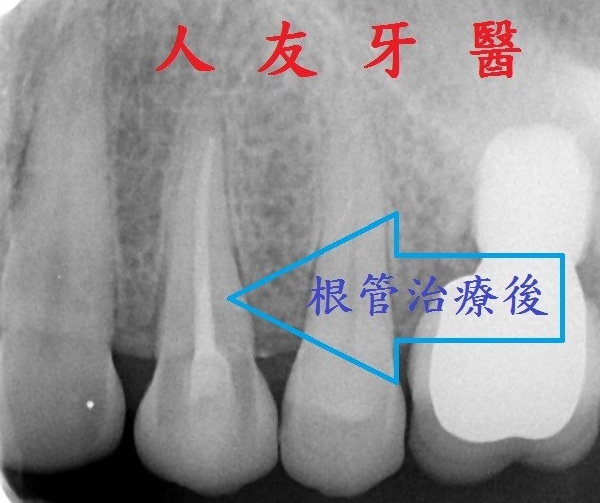

牙齒治療後